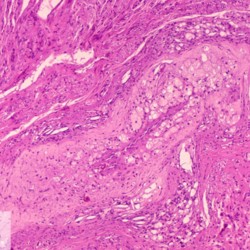

Etiquetes: B-2987/94C 2 total Canine Specie: Canine Organ: Blood vessel Lesion: Atherosclerosis Lesion modifier: - Disease: - Files/Expedient: B-2987/94C Not viewed Canine Specie: Canine Organ: Blood vessel Lesion: Atherosclerosis Lesion modifier: - Disease: - Files/Expedient: B-2987/94C Not viewed Títol Select...Avian (Exotic) (110)Avian (Poultry) (76)Bovine (317)Canine (935)Caprine (47)Equine (257)Feline (326)Ferret (19)General (127)Marine mammal (22)Non-human primate (20)Ovine (328)Porcine (379)Rabbit (61)Reptile (38)Rodent (28)Wildlife (91) Format Select...- (60)Abomasum (37)Adrenal gland (10)Blood (7)Blood vessel (50)Body as a whole (19)Bone (57)Bone marrow (21)Brain (93)Cloaca (1)Diaphragm (2)Ear (5)Esophagus (39)Eye (16)Fetus (12)Gallbladder (23)Gizzard (2)Heart (265)Intestine (356)Joint (32)Kidney (443)Larynx (5)Liver (326)Lung (264)Lymph node (91)Mammary gland (10)Mediastinum (1)Muscle (22)Nasal cavity (22)Nerve (7)Omasum (5)Oral cavity (63)Ovary (14)Oviduct (8)Pancreas (7)Parathyroid (5)Penis (10)Peritoneum (65)Pharynx (9)Pituitary gland (6)Placenta (7)Prostate (8)Proventriculus (3)Reticulum (1)Rumen (28)Sinus (7)Skin (181)Spinal cord (15)Spleen (105)Stomach (125)Teeth (1)Testicle (11)Thoracic cavity (31)Thymus (13)Thyroid gland (5)Tongue (32)Tonsils (11)Trachea (11)Urethra (5)Urinay bladder (61)Uterus (27)Vagina (1)Vulva (1)Yolk sac (1) Cobertura Select...- (152)Abomasitis (26)Abscess (27)Acidosis (1)Adenocarcinoma (20)Adenoma (9)Aerosacculitis (6)Agenesis (1)Agnathia (1)Alopecia (7)Amyloidosis (12)Aneurysm (6)Angiectasis (1)Anthracosis (1)Arteritis (11)Arthritis (15)Arthrogryposis (6)Artifact (4)Ascites (13)Atelectasis (8)Atherosclerosis (5)Atresia (1)Atrial septal defect (2)Atrophy (10)Autolysis (7)Bronchitis (6)Bronchopneumonia (26)Cachexia (2)Carcinoma (103)Cardiomyopathy (19)Cellulitis (2)Chemodectoma (4)Cholangiohepatitis (4)Cholangitis (19)Cholecystitis (4)Cholestasis (5)Chondrodysplasia (2)Chondrosarcoma (2)Chronic passive congestion (13)Chylothorax (2)Cirrhosis (6)Coelomitis (3)Coenurus cerebralis (4)Colitis (40)Congestion (17)Conjunctivitis (5)Coronitis (3)Cryptorchidism (3)Cyst (25)Cystitis (24)Dermatitis (69)Diaphragmatic hernia (4)Dilation (28)Discospondylitis (1)Disseminated intravascular coagulation (7)Dyschondroplasia (1)Dysplasia (29)Ectopia cordis (1)Ectopic ureter (1)Edema (55)Emphysema (5)Encephalitis (5)Endocardiosis (14)Endocarditis (26)Endometritis (5)Enteritis (118)Enterolith (6)Epulis (3)Esophagitis (14)Fasciitis (1)Fibrosis (7)Fibrous osteodystrophy (8)Fistula (1)Folliculitis (3)Fracture (2)Gastritis (34)Gingivitis (5)Glioma (8)Glomerulonephritis (21)Glossitis (25)Glycogenosis (1)Gout (8)Granuloma (2)Granulosa cell tumor (4)Hemangioma (9)Hemangiosarcoma (46)Hematoma (8)Hemoglobinuria (2)Hemopericardium (12)Hemoperitoneum (2)Hemorrhage (100)Hemosiderosis (7)Hemothorax (2)Hepatitis (78)Hernia (11)Histiocytosis (3)Hydatid cyst (11)Hydrocephalus (9)Hydrometra (1)Hydronephrosis (22)Hydropericardium (6)Hydrothorax (3)Hydroureter (5)Hyperkeratosis (8)Hyperostosis (4)Hyperplasia (37)Hypertrophy (9)Hypopigmentation (1)Hypoplasia (7)Hypopyon (1)Impaction (6)Infarction (63)Insulinoma (6)Intussusception (5)Jaundice (17)Laminitis (2)Laryngitis (2)Leiomyoma (5)Leukemia (13)Lipidosis (36)Lipoma (7)Lymphadenitis (45)Lymphadenopathy (7)Lymphangiectasia (6)Lymphangitis (5)Lymphoma (221)Malacia (11)Malignant melanoma (15)Mast cell tumor (11)Mastitis (8)Megaesophagus (2)Melanosis (3)Melena (4)Meningioma (6)Meningitis (6)Meningocele (2)Meningoencephalitis (5)Mesothelioma (5)Methemoglobinemia (2)Mineralization (10)Mucocele (5)Mucometra (1)Multilobular bone tumor (1)Mummification (3)Myelofibrosis (1)Myocarditis (4)Myositis (5)Necrosis (81)Nephritis (113)Nephroblastoma (6)Nephrosclerosis (1)Nephrosis (14)Neuritis (1)Obstruction (13)Omasitis (4)Omphalitis (1)Omphalophlebitis (7)Orchitis (4)Osteoarthrosis (5)Osteomyelitis (9)Otitis (2)Palatoschisis (3)Pancreatitis (3)Panniculitis (3)Papilloma (7)Parakeratosis (14)Patent ductus arteriosus (6)Peliosis hepatis (1)Perforation (17)Pericarditis (35)Peritonitis (39)Persistent right aortic arch (1)Pharyngitis (2)Pheochromocytoma (2)Phlebitis (2)Placentitis (6)Pleuritis (21)Pleuropneumonia (24)Pneumonia (109)Pneumothorax (3)Polycystosis (14)Polyp (5)Polyserositis (6)Posthitis (1)Proctitis (4)Prolapse (3)Prostatitis (3)Proventriculitis (1)Pyelonephritis (24)Pyometra (6)Pyothorax (4)Rhinitis (11)Rumenitis (6)Rupture (24)Salpingitis (3)Sarcoma (57)Sclerosis (1)Scoliosis (2)Seminoma (2)Sequestrum (2)Serous atrophy (14)Sinusitis (7)Splenitis (14)Splenomegaly (9)Spondylitis (6)Spondylosis (1)Stenosis (9)Stomatitis (32)Tenosynovitis (2)Teratoma (3)Thricobezoar (2)Thrombosis (16)Tonsilitis (4)Torsion (13)Tracheitis (4)Tympany (7)Typhlitis (8)Typhlocolitis (4)Ulcer (43)Urethritis (1)Urolithiasis (36)Uroperitoneum (1)Uveitis (1)Vasculitis (15)Ventricular septal defect (3)Volvulus (11) Matèria Select... - (14)- (1653)- (152)Abomasitis - Catarrhal (2)Abomasitis - Catarrhal-hemorrhagic (1)Abomasitis - Chronic (1)Abomasitis - Fibrinous-necrotizing (2)Abomasitis - Hyperplasic (5)Abomasitis - Hyperplasic - Chronic (1)Abomasitis - Necrotic (1)Abomasitis - Necrotizing (2)Abomasitis - Ulcerative (5)Adenocarcinoma (9)Aerosacculitis - Granulomatous (1)Amyloidosis - Chronic (1)Arteritis - Necrotic (2)Arteritis - Necrotizing (1)Arthritis - Chronic (4)Arthritis - Fibrinous-purulent (3)Arthritis - Serous (4)Arthritis - Subacute (1)Ascites - Serous (1)Atrophy - Serous (1)Bronchitis - Catarrhal (3)Bronchitis - Suppurative (1)Bronchopneumonia - Catarrhal-purulent (17)Bronchopneumonia - Fibrinous (1)Bronchopneumonia - Granulomatous (1)Bronchopneumonia - Purulent (1)Bronchopneumonia - Suppurative (5)Carcinoma - Adenocarcinoma (33)Carcinoma - Adenocarcinoma - Hepatocellular (2)Carcinoma - Adenocarcinoma - Mucinous (1)Carcinoma - Basosquamous (1)Carcinoma - Cholangiocellular (3)Carcinoma - Hepatocellular (4)Carcinoma - Metastatic (3)Carcinoma - Squamous cell carcinoma (13)Carcinoma - Transitional cell (2)Cardiomyopathy - Dilated (13)Cardiomyopathy - Hypertrophic (6)Cellulitis - Necrotizing (1)Cholangitis - Chronic (8)Cholangitis - Hyperplasic (3)Cholecystitis - Fibrinous-necrotizing (1)Coelomitis - Fibrinous (1)Coelomitis - Granulomatous (1)Colitis - Catarrhal (3)Colitis - Catarrhal-hemorrhagic (1)Colitis - Fibrinous (1)Colitis - Fibrinous-necrotizing (1)Colitis - Fibrinous-necrotizing (Diphtheritic) (6)Colitis - Granulomatous (2)Colitis - Hemorrhagic (4)Colitis - Hemorrhagic-necrotizing (3)Colitis - Necrotizing (2)Colitis - Ulcerative (6)Congestion - Chronic (2)Conjunctivitis - Hyperplasic (1)Conjunctivitis - Purulent (3)Coronitis - Ulcerative (1)Cystitis - Chronic (3)Cystitis - Fibrinous (1)Cystitis - Fibrinous-necrotizing (1)Cystitis - Follicular (1)Cystitis - Hemorrhagic (6)Cystitis - Hemorrhagic-ulcerative (1)Cystitis - Necrotizing (9)Cystitis - Perforated (1)Dermatitis - Granulomatous (14)Dermatitis - Hyperkeratotic (10)Dermatitis - Hyperplasic (proliferative) (1)Dermatitis - Hyperplastic (10)Dermatitis - Necrotizing (4)Dermatitis - Pustular (4)Dermatitis - Ulcerative (2)Dilation - Chronic (1)Discospondylitis - Necrotizing (1)Dysplasia - Follicular (5)Edema - Interstitial (6)Emphysema - Interstitial (1)Encephalitis - Granulomatous (1)Encephalitis - Nonsuppurative (1)Endocardiosis - Mitral (7)Endocardiosis - Mitral - Chronic (5)Endocarditis - Valvular (6)Endocarditis - Valvular - Mitral (7)Endocarditis - Valvular - Pulmonic (1)Endocarditis - Valvular - Subacute (1)Endocarditis - Valvular - Subaortic (5)Endocarditis - Valvular - Tricuspid (4)Endometritis - Purulent (3)Endometritis - Purulent-hemorrhagic (2)Enteritis - Catarrhal (23)Enteritis - Catarrhal - Acute (1)Enteritis - Catarrhal-hemorrhagic (5)Enteritis - Catarrhal-hemorrhagic - Acute (2)Enteritis - Fibrinous (16)Enteritis - Fibrinous - Acute (3)Enteritis - Fibrinous-necrotizing (7)Enteritis - Granulomatous (14)Enteritis - Granulomatous - Chronic (1)Enteritis - Granulomatous - Multifocal (1)Enteritis - Hemorrhagic (17)Enteritis - Hemorrhagic - Acute (1)Enteritis - Hemorrhagic-necrotizing (1)Enteritis - Hyperplasic (proliferative) (4)Enteritis - Necrotizing (4)Enteritis - Necrotizing - Acute (1)Enteritis - Necrotizing - Hemorrhagic (1)Enteritis - Necrotizing-ulcerative (2)Enteritis - Ulcerative (1)Enteritis - Ulcerative-hemorrhagic (1)Esophagitis - Erosive-ulcerative (6)Esophagitis - Necrotizing (4)Esophagitis - Ulcerative (1)Esophagitis - Ulcerative-necrotizing (1)Fasciitis - Fibrinous-purulent (1)Folliculitis - Purulent (2)Gastritis - Catarrhal (2)Gastritis - Chronic (1)Gastritis - Follicular (1)Gastritis - Hemorrhagic (2)Gastritis - Hemorrhagic-necrotizing (1)Gastritis - Hypertrophic (2)Gastritis - Inclusion bodies (1)Gastritis - Mineralization (1)Gastritis - Mycotic (1)Gastritis - Necrotizing (2)Gastritis - Ulcerative (6)Gastritis - Uremic (3)Gingivitis - Erosive (2)Gingivitis - Hyperplasic (proliferative) (1)Gingivitis - Necrotizing (1)Glomerulonephritis - Chronic (7)Glomerulonephritis - Membranoproliferative (3)Glomerulonephritis - Membranoproliferative - Chronic (1)Glomerulonephritis - Membranous (3)Glomerulonephritis - Membranous - Chronic (1)Glomerulonephritis - Proliferative (2)Glomerulonephritis - Subacute (1)Glossitis - Erosive (2)Glossitis - Granulomatous (6)Glossitis - Hyperplasic (1)Glossitis - Hyperplasic (proliferative) (2)Glossitis - Hyperplastic (1)Glossitis - Necrotizing (2)Glossitis - Necrotizing - Focal (1)Glossitis - Ulcerative (6)Glossitis - Ulcerative - Multifocal (1)Glossitis - Ulcerative - Subacute (1)Glycogenosis (1)Granuloma - Eosinophilic (1)Hemangiosarcoma - Metastatic (2)Hemorrhage - Acute (1)Hemorrhage - Subcapsular (3)Hepatitis - Abscess (9)Hepatitis - Acute (3)Hepatitis - Chronic (4)Hepatitis - Chronic interstitial (6)Hepatitis - Granulomatous (7)Hepatitis - Interstitial - Multifocal (1)Hepatitis - Interstitial - Subacute (1)Hepatitis - Necrotizing (17)Hepatitis - Necrotizing - Acute (2)Hepatitis - Necrotizing - Hemorrhagic (1)Hepatitis - Necrotizing - Subacute (1)Hepatitis - Pyogranulomatous (7)Hepatitis - Subacute (4)Hydronephrosis - Chronic (1)Hydropericardium - Chronic (1)Hyperplasia - Erythroid (1)Hyperplasia - Lymphoid (3)Hyperplasia - Myeloid (1)Hyperplasia - Nodular (8)Hypertrophy - Concentric (2)Hypertrophy - Eccentric (3)Infarction - Acute (17)Infarction - Acute - Multifocal (2)Infarction - Chronic (5)Infarction - Chronic - Multifocal (1)Infarction - Subacute (18)Infarction - Subacute - Focal (2)Laminitis - Chronic (2)Laryngitis - Necrotic (1)Laryngitis - Necrotizing (1)Leukemia - Lymphoid leukemia (2)Leukemia - Non-lymphoid leukemia (6)Lipidosis - Multifocal (1)Lipidosis - Panlobular (1)Lipidosis - Panlobular - Generalized (2)Lymphadenitis - Granulomatous (24)Lymphadenitis - Granulomatous - Chronic (3)Lymphadenitis - Hemorrhagic (1)Lymphadenitis - Necrotizing (5)Lymphadenitis - Necrotizing (caseous) (11)Lymphangitis - Granulomatous (1)Lymphangitis - Purulent (1)Lymphangitis - Ulcerative (1)Lymphoma - Alimentary lymphoma (7)Lymphoma - Cutaneous lymphoma (6)Lymphoma - Lymphosarcoma (2)Lymphoma - Mediastinal lymphoma (1)Lymphoma - Multicentric lymphoma (29)Malignant melanoma - Malignant (1)Malignant melanoma - Metastatic (1)Mast cell tumor - Metastatic (1)Mastitis - Fibrinous-purulent (2)Mastitis - Necrotic (1)Mastitis - Purulent (3)Mastitis - Suppurative (1)Meningitis - Fibrinous-purulent (2)Meningitis - Purulent (4)Meningoencephalitis - Necrotizing (3)Meningoencephalitis - Nonsuppurative (2)Mineralization - Metastatic (4)Myocarditis - Fibrous - Chronic (1)Myocarditis - Granulomatous (1)Myositis - Purulent (2)Necrosis - Acute (1)Necrosis - Cortical (5)Necrosis - Follicular (1)Necrosis - Papillary (8)Necrosis - Papillary - Acute (3)Necrosis - Subacute (3)Necrosis - Tubular (6)Nephritis - Embolic (2)Nephritis - Embolic suppurative (7)Nephritis - Granulomatous (27)Nephritis - Granulomatous - Chronic (1)Nephritis - Granulomatous - Multifocal (1)Nephritis - Interstitial (6)Nephritis - Interstitial - Acute (4)Nephritis - Interstitial - Chronic (41)Nephritis - Interstitial - Subacute (12)Nephritis - Purulent (7)Nephritis - Purulent - Acute (2)Nephritis - Purulent - Multifocal (3)Nephrosis - Cholemic (3)Nephrosis - Hemoglobinuric (10)Omasitis - Fibrinous-necrotizing (1)Omasitis - Hyperkeratotic (1)Omasitis - Necrotizing (2)Omphalophlebitis - Fibrinous-purulent (2)Omphalophlebitis - Purulent (3)Orchitis - Necrotizing (1)Osteomyelitis - Necrotizing (7)Osteomyelitis - Purulent (2)Otitis - Necrotizing (1)Otitis - Proliferative (1)Pancreatitis - Acute (1)Pancreatitis - Chronic (1)Pancreatitis - Granulomatous (1)Panniculitis - Fibrinous-purulent (1)Panniculitis - Necrotic (1)Panniculitis - Parasitic (1)Perforation - Acute (2)Pericarditis - Fibrinous (19)Pericarditis - Fibrinous - Subacute (1)Pericarditis - Fibrinous-necrotizing (1)Pericarditis - Fibrinous-purulent (3)Pericarditis - Fibrous (1)Pericarditis - Fibrous - Chronic (1)Pericarditis - Gangrenous (6)Pericarditis - Granulomatous (1)Pericarditis - Granulomatous - Chronic (2)Peritonitis - Acute (1)Peritonitis - Fibrinous (11)Peritonitis - Fibrinous - Subacute (1)Peritonitis - Fibrinous-purulent (5)Peritonitis - Fibrous (3)Peritonitis - Granulomatous (6)Peritonitis - Purulent (1)Peritonitis - Purulent-hemorrhagic (1)Peritonitis - Pyogranulomatous (3)Pharyngitis - Fibrinous-necrotizing (1)Pharyngitis - Ulcerative (1)Pheochromocytoma - Metastatic (1)Phlebitis - Purulent (1)Placentitis - Fibrinous-necrotizing (1)Placentitis - Necrotic (1)Placentitis - Necrotizing (1)Pleuritis - Chronic (1)Pleuritis - Fibrinous (3)Pleuritis - Fibrinous-purulent (2)Pleuritis - Fibrous (2)Pleuritis - Granulomatous (3)Pleuritis - Hyperplastic (2)Pleuritis - Purulent (2)Pleuritis - Pyogranulomatous (1)Pleuropneumonia - Fibrinous (13)Pleuropneumonia - Fibrinous-necrotizing (5)Pleuropneumonia - Granulomatous (2)Pleuropneumonia - Hemorrhagic-necrotizing (4)Pneumonia - Aspiration (11)Pneumonia - Bronchointerstitial (4)Pneumonia - Bronchointerstitial - Subacute (1)Pneumonia - Embolic (5)Pneumonia - Granulomatous (37)Pneumonia - Granulomatous - Multifocal (4)Pneumonia - Hemorrhagic-necrotizing (2)Pneumonia - Interstitial (7)Pneumonia - Interstitial - Acute (8)Pneumonia - Interstitial - Chronic (6)Pneumonia - Interstitial - Subacute (15)Pneumonia - Necrotizing (2)Pneumonia - Pyogranulomatous (2)Pneumonia - Verminous (5)Polyserositis - Fibrinous (6)Polyserositis - Fibrous (1)Proctitis - Fibrinous-necrotizing (1)Proctitis - Parasitic (2)Prostatitis - Purulent (1)Pyelonephritis - Acute (2)Pyelonephritis - Chronic (3)Rhinitis - Catarrhal (2)Rhinitis - Fibrinous (1)Rhinitis - Granulomatous (4)Rhinitis - Purulent (3)Rumenitis - Acute (1)Rumenitis - Erosive (1)Rumenitis - Necrotizing (1)Rupture - Acute (3)Sarcoma - Fibrosarcoma (12)Sarcoma - Hemangiosarcoma (11)Sarcoma - Histiocytic (7)Sarcoma - Metastatic (1)Sarcoma - Multilobular tumor of bone (1)Sequestrum - Chronic (2)Sinusitis - Suppurative (1)Splenitis - Granulomatous (8)Splenitis - Granulomatous - Chronic (1)Splenitis - Necrotizing (3)Splenitis - Necrotizing (caseous) (2)Spondylitis - Necrotizing (2)Stenosis - Intestinal (1)Stenosis - Valvular - Subaortic (4)Stomatitis - Erosive (12)Stomatitis - Erosive-ulcerative (3)Stomatitis - Fibrinous-necrotizing (1)Stomatitis - Fibrinous-necrotizing (Diphtheritic) (1)Stomatitis - Granulomatous (1)Stomatitis - Hyperplasic (1)Stomatitis - Hyperplasic (proliferative) (1)Stomatitis - Necrotizing (2)Stomatitis - Ulcerative (5)Stomatitis - Ulcerative - Multifocal (1)Stomatitis - Ulcerative-necrotizing (1)Tonsilitis - Necrotizing (4)Torsion - Acute passive hyperemia (5)Tracheitis - Catarrhal (3)Tracheitis - Fibrinous (1)Tracheitis - Granulomatous (1)Typhlitis - Catarrhal (1)Typhlitis - Fibrinous-necrotizing (2)Typhlitis - Hemorrhagic (2)Typhlitis - Ulcerative-hemorrhagic (1)Typhlocolitis - Fibrinous-necrotizing (2)Typhlocolitis - Proliferative (1)Ulcer - Chronic (6)Ulcer - Multifocal (2)Ulcer - Mycotic (1)Ulcer - Perforated (6)Urethritis - Hemorrhagic (1)Urolithiasis - Chronic (2)Uveitis - Granulomatous (1)Vasculitis - Granulomatous (1)Vasculitis - Necrotizing (1) Editor Select...- (1970)Acidosis (2)Actinobacillosis (Pleuropneumonia) (11)Aelurostrongylosis (2)African horse sickness (13)African swine fever (14)Alopecia X (1)Anaplasmosis (4)Anthrax (2)Aortic thromboembolism (feline) (7)Ascariasis (15)Aspergillosis (18)Atopic dermatitis (1)Atrophic rhinitis (3)Babesiosis (6)Blackhead (1)Bluetongue (11)Border disease (2)Bovine viral diarrhea (21)Brucellosis (2)Candidiasis (5)Canine distemper (14)Caprine arthritis-encephalitis (2)Capture myopathy (1)Cardiac insufficiency (17)Caseous lymphadenitis (7)Chlamydiosis (2)Classical swine fever (19)Clostridiosis (19)Coccidiosis (9)Coenurosis (4)Colibacillosis (21)Contagious ecthyma (7)Copper toxicosis (11)Cowdriosis (Heartwater) (3)Cryptococcosis (3)Cryptosporidiosis (2)Cysticercosis (23)Demodicosis (1)Diabetes (1)Dicrocoeliosis (5)Dictyocaulosis (4)Dirofilariasis (7)Discoid lupus erythematosus (3)Echinococcosis (17)Edema disease (7)Egg drop syndrome (1)Encephalitozoonosis (5)Enterotoxemia (1)Enzootic bovine leukosis (46)Epitheliogenesis imperfecta (3)Equine rhinopneumonitis (2)Equine verminous arteritis (strongylosis) (7)Erysipelas (5)Exudative epidermitis (7)Fasciolasis (11)Feline eosinophilic dermatoses (1)Feline hepatic lipidosis (8)Feline histiocytosis (4)Feline infectious peritonitis (38)Feline leukemia (4)Feline lower urinary tract disease (3)Feline panleukopenia (16)Feline viral rhinotracheitis (1)Flea allergy dermatitis (1)Foot and mouth disease (2)Gasterophilosis (4)Glasser's disease (15)Gousiekte (4)Gout (6)Haemonchosis (9)Hemolytic anemia (4)Hemorrhagic diathesis (1)Hepatic insufficiency (11)Hepatosis dietetica (7)Herpesvirosis (6)Hyperadrenocorticism (7)Hyperparathyroidism (10)Hypertrophic osteopathy (6)Hypervitaminosis D (1)Hypodermosis (1)Inclusion body hepatitis (4)Infectious bovine rhinotracheitis (5)Infectious bronchitis (5)Infectious canine hepatitis (13)Influenza (4)Juvenile nephropathy (8)Lamb dysentery (4)Leishmaniasis (28)Leptospirosis (1)Leukosis (5)Listeriosis (4)Lumpy skin disease (3)Maedi-visna (4)Malignant catarrhal fever (12)Mange (6)Mannheimiosis (5)Marek's disease (7)Metabolic bone disease (2)Mucoid enteropathy (5)Mulberry heart disease (5)Myasis (1)Mycobacteriosis (22)Mycosis fungoides (6)Myxomatosis (3)Necrobacillosis (5)Neonatal isoerythrolysis (6)Nocardiosis (4)Oestrosis (2)Onchocerciasis (1)Osteochondrosis (1)Ostertagiosis (6)Ovine pulmonary adenocarcinoma (5)Oxyuriasis (1)Pacheco's disease (4)Papillomatosis (6)Paratuberculosis (18)Parvovirosis (17)Pasteurellosis (11)Pemphigus foliaceus (1)Periodontal disease (1)Polioencephalomalacia of ruminants (4)Polyarteritis nodosa (3)Polycystic kidney disease (13)Porcine circovirosis (11)Porcine dermatitis and nephropathy syndrome (9)Porcine proliferative enteropathy (4)Porcine reproductive and respiratory syndrome (6)Porcine stress syndrome (1)Pox (13)Pregnancy toxemia (3)Proventricular dilatation disease (2)Pseudotuberculosis (yersiniosis) (2)Psittacine beak and feather disease (PBFD) (5)Pyoderma (4)Q fever (4)Rabbit hemorrhagic disease (2)Renal insufficiency (12)Reticuloendotheliosis (2)Rhodococcosis (1)Rickets (1)Rinderpest (2)Salmonellosis (34)Sarcosporidiosis (2)Schmallenberg (7)Septicemia (23)Spirocercosis (11)Streptococcosis (5)Strongylosis (1)Swine dysentery (5)Systemic coronavirosis (5)Tetralogy of Fallot (5)Theileriosis (13)Thromboembolism (5)Toxoplasmosis (11)Transmissible viral proventriculitis (1)Traumatic reticuloperitonitis (3)Traumatism (16)Tuberculosis (58)Ulcerative lymphangitis (1)Uremic syndrome (20)Viral arthritis (6)White muscle disease (9)Wobbler syndrome (2)Xanthomatosis (1)Zygomycosis (4) Idioma Select...- (1180)Bacterial (501)Degeneration (106)Fungal (46)Hemodynamic (112)Idiopathic (22)Inflammation (58)Malformation (88)Neoplasia (343)Nutritional (41)Parasitic (243)Physical/Chemical (93)Toxic (44)Viral (304) Ítem destacat Porcine Sow. Porcine Ulcerative Dermatitis Syndrome (PUDS). Interface dermatitis. Lesions were neither painful nor pruritic. University of Pretoria, South…